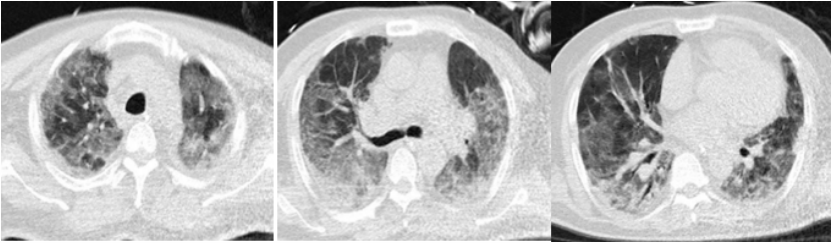

84岁男性患者,既往冠心病、陈旧性心肌梗死,未接种新冠疫苗。2022年12月15日起病,12月27日诊断为COVID-19,Paxlovid治疗5 d停用,同时抗炎。2023年1月9日肺部病变吸收,予以出院。

1月26日再次发热、呼吸困难加重,铁蛋白513.5 ng/ml,IL-6 3834.49 pg/ml。入院后细菌、真菌、病毒的病原学检查均为阴性,未找到继发感染的证据。ANCA+ANA、肌炎抗体谱均阴性。予甲强龙80 mg qd 3 d,后改为40 mg qd。治疗后炎症指标逐渐下降,影像学吸收。

图片

患者影像学变化

该患者第一次出院后应继续抗炎治疗,可能由于抗炎疗程不足,导致出现了炎症的“反弹”。